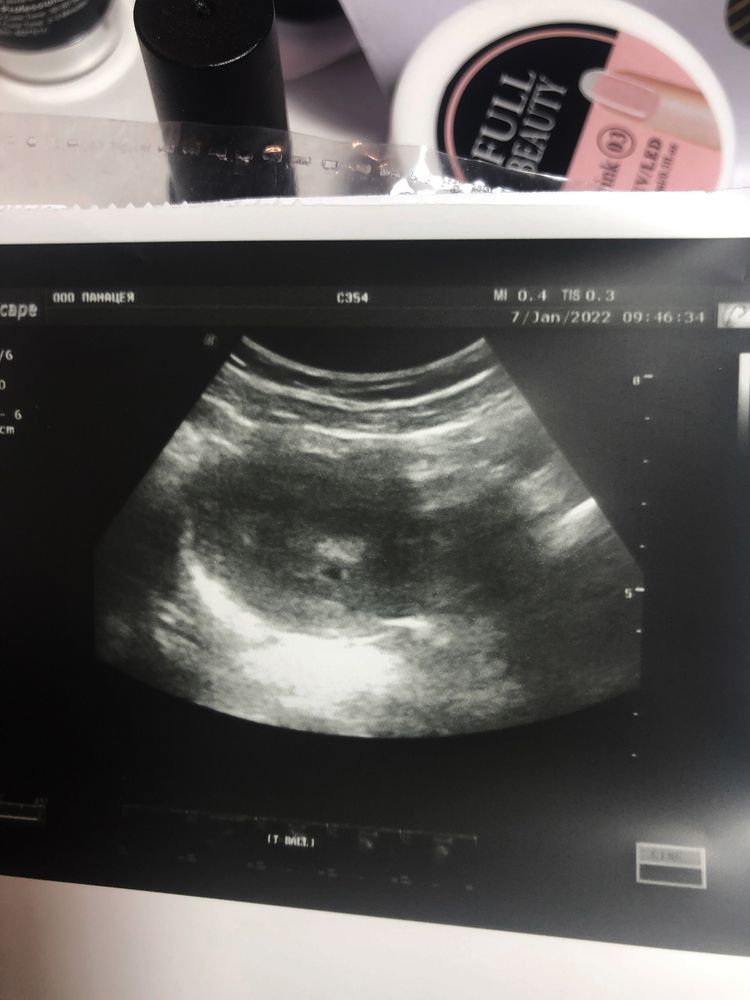

Двойня ?

Подскажите пожалуйста ,это может быть двойняшки ?

Узист сказал что матка расширена не на свой срок, больше

Срок 3-4 недели ,может кто сталкивался с таким

Сказал прийти на приём через 2 недели ,но за многоплодную беременность не сказал ничего 🤔